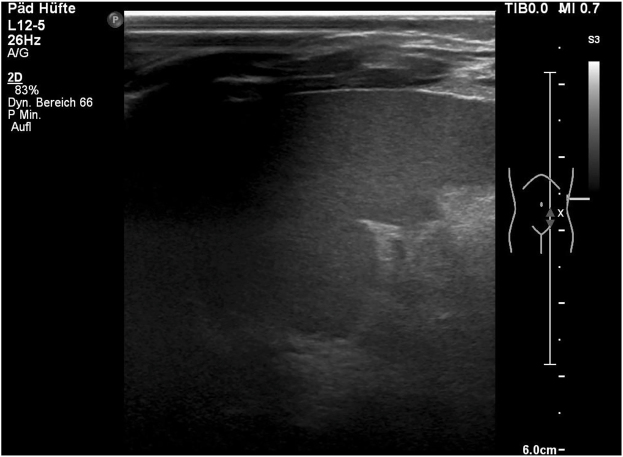

Case presentation: We report a rare case of excessive neonatal weight in a medically unsupervised pregnancy and give a literature review on this significant subject. A 38 year-old woman (Gravida 8 Para 7) presented herself at 42 2/7 weeks of gestation at the labor ward. The pregnancy had not been supervised medically. Labor induction was initiated. Due to failure to progress and suspicion of a disproportion of the fetal head and maternal pelvis an urgent caesarean section was performed. A morbidly macrosomic male infant was delivered (birth weight: 6,760 g [>99. percentile], length: 60 cm [>99. percentile]).